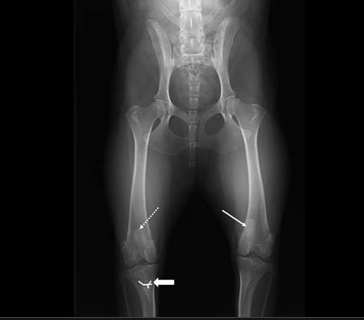

슬개골 탈구 진단은 병원에서 상담 중에 개에 대한 신체 검사를 수행할 수의사가 진단합니다. 검사하는 동안 수의사는 진단을 확인하기 위해 슬개골을 제자리에서 조작할 수 있습니다. 어떤 경우 에는 무릎 관절을 평가하기 위해 X-레이 가 필요할 수 있습니다.

내측 탈구 슬개골은 정도에 따라 1~4등급으로 나뉩니다. (등급이 높으면 심각한 상태)

경골 능선을 더 측면 위치로 이동(슬개골 메커니즘을 곧게 펴기 위해 옆으로 이동) 이것은 하나 또는 두 개의 작은 핀과 장력을 유지하기 위한 와이어 조각으로 제자리에 고정됩니다.